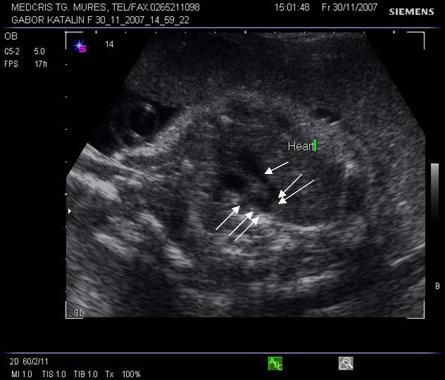

Fig. nr 183. La examenul Doppler, se poate stabili integritatea septului ventricular, in sectiunea cord in 4 camere